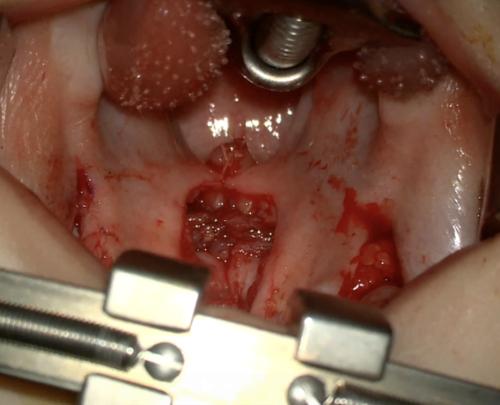

![]() ▲ 사진은 남승민 교수가 중첩형 연구개 근육재배열수에서 근육 재배열을 안료한 모습이다. |

하지만 남승민 교수는 이들 수술 대신 ‘중첩형 연구개근육 재배열술(Overlapping Intravelar veloplasty)’을 시행했다. 중첩형 연구개근육 재배열 수술은 입천장 올림근의 근육을 현미경을 이용해 세밀하게 박리해 이를 중첩해 수술하는 방법이다.